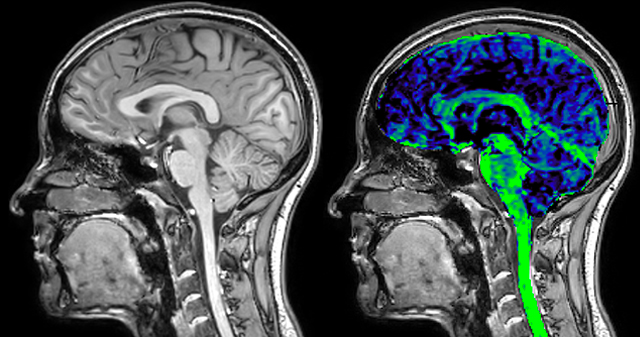

T1 - Weighted, Myelin Water Fraction Superimposed

Spinal cord coverage

Smaller, more isotropic voxels

Excellent detail in quantitative maps

Images courtesy of Adam Dvorak, Department of Physics and Astronomy, University of British Columbia

of limiting MWI to the brain, even without the cerebellum, we can now spend about the same amount of time and scan the whole brain and the cervical spinal cord, which is a huge boost for us.” Dr. Rauscher says, “For MWI we perform 3D T2 with 32 or more echoes. This used to take a long time, but with Compressed SENSE we can decrease this to ten minutes for the whole head. Because of the large field of view (FOV) on the readout direction, we even get information from the brainstem, which we previously missed when we were using the GRASE approach. Having the whole head scan is nice because it has spatial resolution, orientation and FOV that are comparable to the standard 3D clinical MS scans, including the FLAIR and 3D T2, and a 3D T1 for brain volume.”

The techniques for measuring myelin have changed a lot over the years. “Since we are using the Elition, our myelin water images are much better. We're now acquiring 1 x 2 x 5 mm voxels and displaying at 1 x 1 x 2.5 mm. For a whole brain we can now measure the fraction of water in the myelin component in only about five or six minutes,” Dr. MacKay says.